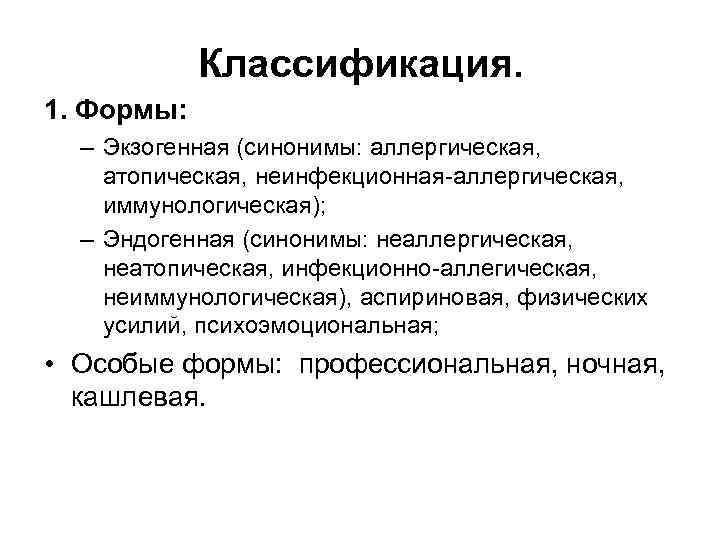

Классификация. 1. Формы: – Экзогенная (синонимы: аллергическая, атопическая, неинфекционная-аллергическая, иммунологическая); – Эндогенная (синонимы: неаллергическая, неатопическая, инфекционно-аллегическая, неиммунологическая), аспириновая, физических усилий, психоэмоциональная; • Особые формы: профессиональная, ночная, кашлевая.